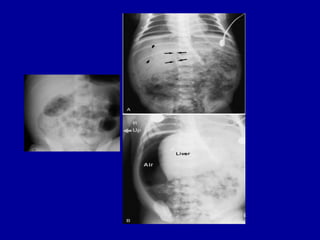

12.52 pm AXR

•  ADDENDUM

•  Review of the images reveal air lucency noted in both hypochondrial regions

which

• are worrisome for free gas. There is also suggestion of portal venous gas.

• ***FINAL ADDENDUM***

Verified by: Dr PCC, Registrar,

• Amended Date/Time: 30-MAR-2005 09:27

•   ORIGINAL REPORT

•   HISTORY

• High NG aspirates

•   REPORT

•   The small bowel loops are dilated and there is faecal material noted in the large

•   colon but not much in the rectum. However, no definite pneumotosis intestinalis

•   is seen. Tip of the NG tube is in the distal oesophagus rather than the stomach

•   and should be adjusted.

•   CONCLUSION

•   The small bowel is dilated. The cause however is not visualised in the study.

15.52 pm AXR

•   ? sepsis. Growing prem. Abdominal distension.

•   CXR - MOBILE SUPINE AP

•   Compared with CXR from 14/12/2004.

•   NG tube is again noted. There is now bilateral perihilar peribronchial thickening.

•   Cardiac size is unremarkable.

•   The intestinal loops remained gaseously distended though faecal matter is seen within

•   the colon. There is a lack of rectal air through a catheter is seen in the lower

•   pelvic cavity.

22.40 pm

•   Septicaemia. NEC. Intubated.

•   MOBILE SUPINE (CHEST AND ABDOMEN)

•   The tip of the NG tube is projected over the distal esophagus. The tip of the ETT

•   is about 0.6cm from the carina.

•   A tube is projected over the rectal area.

•   There is diffuse haziness of both lungs. The heart size cannot be assessed.

•   There are multiple gas distended intestinal loops and intraperitoneal free gas present

•   which appears worse when compared to the last AXR.

1.44 am

•   NEC, septic shock on CPAP, IA and IV lines.

•   AXR - SUPINE AP

•   Compared with AXR taken 10 hours earlier.

•   The nasogastric tube is now seen projected over the left hypochondrium. There is

•   interval worsening of the gaseously distended intestinal loops. Faecal matter is

•   again seen in the proximal colon. No air or faecal matter seen in the pelvic cavity.

•   There is free extraluminal air within the peritoneal cavity, outlining the liver.

•   Rigler's sign is noted, consistent with intestinal perforation.